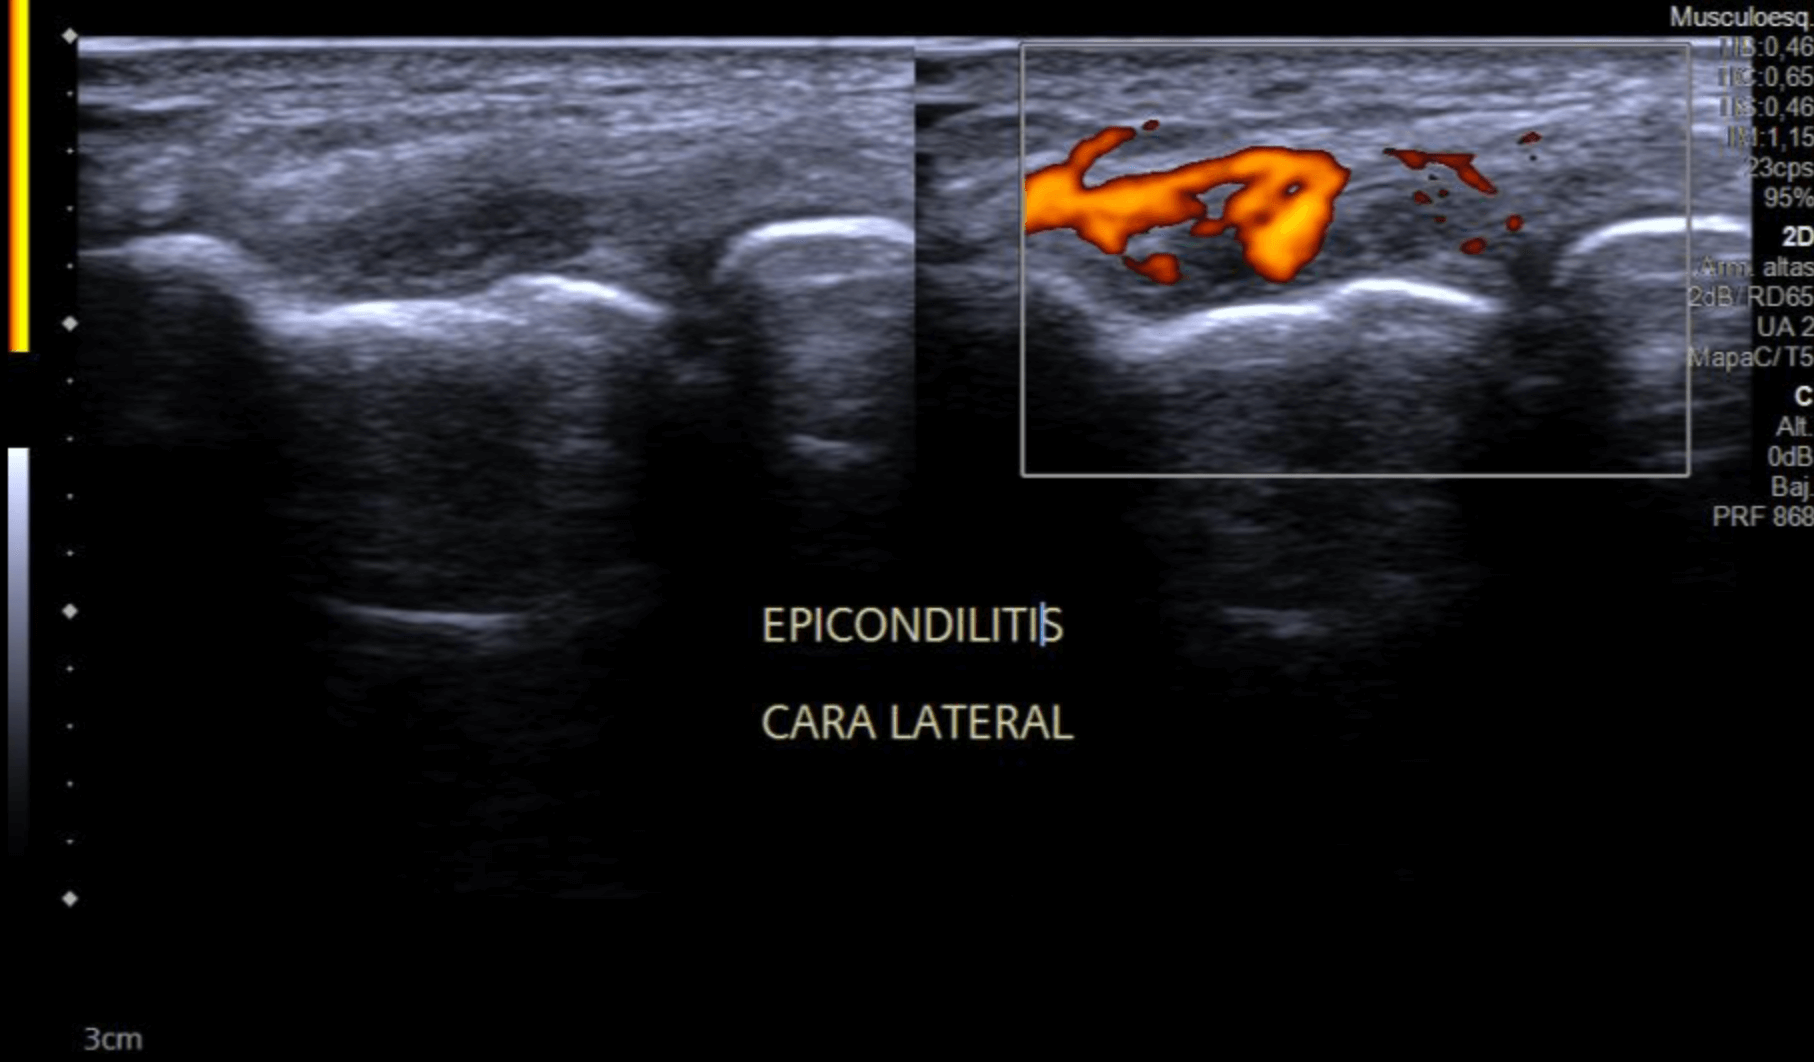

Ecografía de Codo: Epicondilitis Codo.